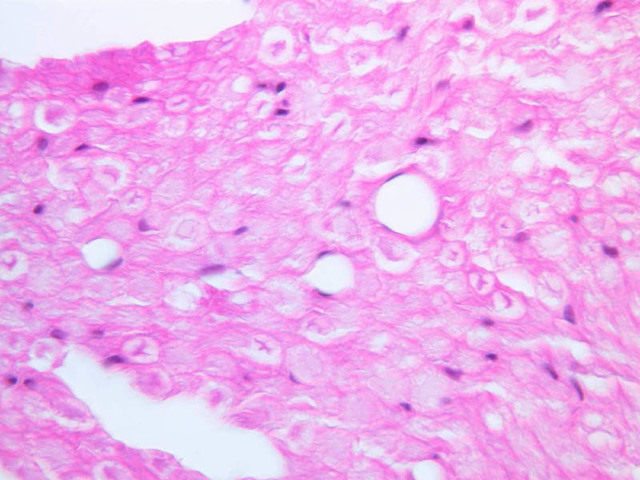

On Slide A-79 notice the choroid plexus ([2.5x, 10x, 20x, 40x] [2.5x, 10x, 20x, 40x]), a coiled structure located in the fourth ventricle, which is at the base of the cerebellum. The choroid plexus is a tangled mass of blood vessels and modified ependymal cells that is responsible for producing cerebrospinal fluid.